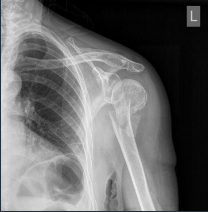

Rx assessment of Fr (peculiar types)

According to AGE

Elderly: OP

Skin status: closed / open

Rx assessment of Fr alignment (dislocation)

Lateral

Angulation

Rotation

Longitudinal (along the bone axis)

Distancing

Intermission

AScent (straddling)

Rx assessment Fr appearance and course

APPEARANCE

Fissure (subtle)

Complete (total disruption)

Incomplete (ONLY one cortical disrupted)

COURSE (single or multiple)

Transverse (diaphysis)

Oblique (bending)

Helical (torsion)

Cominuted

Layered

Rx assessment of Fr location

Rx assessment of Fractures

Loc (anatomic)

Extent

Type (complete / incomplete)

Course (carry): fr line VS bone long axis

Aligment bone fragments (annulation, rotation, ascent, spacing)

Special types

Skin

Assoc lesions (Fr + luxation / spacing)